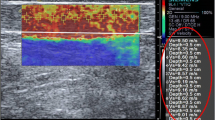

Two observers participated in this study and both of them used the same ultrasound system (LOGIQ E9; GE Medical Systems, Wisconsin, USA) with a 9-MHz linear probe. The first observer (HNS, 11 years experienced in musculoskeletal radiology) performed B-mode ultrasound and measured thickness of bilateral CETs (n = 60) of all volunteers at the level of the humeroradial joint and then used the SWE imaging to measure the stiffness values of all subjects in kPa consecutively (Figs. 1, 2). The second observer (EC, 10 years experienced in musculoskeletal radiology) performed only elastographic evaluation of all CETs just after the first examination had ended. The observers were blind to their results. All the volunteers were examined in the sitting position with 90° flexion of elbow and the thumbs up. The tip of the linear probe was covered with a generous amount of ultrasound gel and to avoid anisotropy, the probe was placed parallel to the longitudinal axis of the CET. The stiffness measurements were made by using 2-mm region of interest (ROI) at the level of the capitellar region. All ROIs included only the tendon structure. CET stiffness values were measured three times by both observers and the median of the consecutive three measurements was recorded. Consecutive measurements were made from approximately the same area of the tendon at the capitellar region on different elastography images.

The demographic characteristics of the participants are presented in Table 1. Mean age of the participants was 30.2 years (age range 21 to 48). All CETs demonstrated normal fibrillar echotexture, straight contours, and none of them included any sonographic abnormality that could be associated with lateral epicondylopathy. The mean thickness of CETs was 3.57 ± 0.36 mm. Age, sex, height, and dominant hand had no significant correlation with tendon thickness. Tendon thickness had a weak correlation with weight (r = 0.281, p = 0.03). The mean stiffness values of CETs for two observers were 45.28 ± 9.82 kPa and 45.80 ± 9.72 kPa respectively. Table 2 summarizes the measurements. Age, sex, weight, height, and dominant hand had no significant effects on SWE measurements. There was a moderate correlation between tendon thickness and stiffness values (r = 0.429, p < 0.001). Figure 3 presents Bland–Altman plots of pairs of stiffness measurements that show the 95% limits of agreement and median of differences for interobserver variability. The mean interobserver difference of CET stiffness measurements was −0.5% of the mean CET stiffness values. Range of measurement error, defined as 95% limits of agreement, was ±23.5%. There was no significant difference between absolute values of interobserver measurements (p = 0.741).

Bland–Altman plots of common extensor tendon (CET) stiffness measurements by two observers. Difference in stiffness values between observers 1 and 2 is plotted against the mean CET stiffness values of two observers. The red line indicates the mean difference of all measurements (n = 60) and the green lines denote 95% limits of agreement (mean ± 1.96 SD)